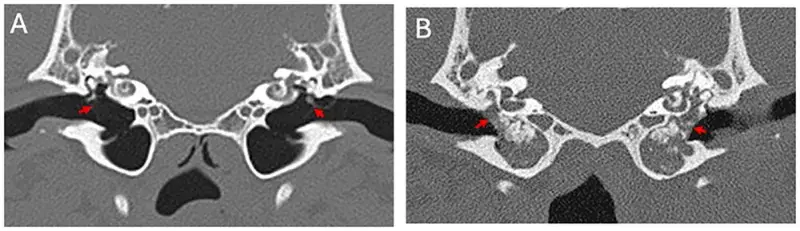

Deep learning models trained on scan images can aid vets in managing caseloads. AI tools can support vets in diagnosing disease, research has shown.A computer model has been trained to recognise a common disease in dogs with an encouraging success rate, underscoring its potential as a veterinary tool.The approach supports the use of AI for relatively straightforward tasks, to allow vets to concentrate on more complex tasks, according to the team behind the study. Scan images Researchers from the Royal (Dick) School of Veterinary Studies, the Roslin Institute and the University of Edinburgh’s School of Informatics developed their model using CT scan images of dogs’ middle ears – a part of the ear that is frequently affected by disease.The model was trained to recognise disease using about 500 images, some that showed signs of disease and others that did not, which had been manually interpreted by veterinary experts. This number is fewer than the several thousands that would typically be needed for many AI studies, which would be resource-intensive to generate.The AI tool was able to make correct diagnoses in 85 per cent of cases. Experts say the result is robust for a relatively small sample size, demonstrating the validity of the approach, and could be improved if additional images were annotated. AI can be deployed to diagnose disease with reliable accuracy. Diagnosis potential The application of AI in this way, which is established in human medicine, could be made to various veterinary medicine challenges, potentially including those that are traditionally difficult to diagnose by eye. This would save time and money in making diagnoses, the team says.A bank of veterinary medical images, annotated by vets, would be required to enable adoption of AI in veterinary diagnoses, and could be applied across a range of conditions, the team suggests. Vet schools and hospitals such as the R(D)SVS have banks of images, but a sufficient number have to be annotated to train algorithms.The study was conducted by a masters degree student in the School of Informatics. Our study showed that deep learning computer models can be trained to determine whether or not disease is present in a veterinary CT image. Even training our model on a relatively small number of images had encouraging results.This outcome is a call to arms to gather resources to enable models of this type, for various veterinary conditions. Dr Chris Banks, Roslin Institute This is a great example of how AI can be put to use to help veterinarians, rather than replace them. Dr Tobias Schwarz, Royal (Dick) School of Veterinary Studies This article was first published by the Royal (Dick) School of Veterinary Studies on 10 September 2025 Related links Link to paper The Royal (Dick) School of Veterinary Studies The Roslin Institute Publication date 09 Sep, 2025